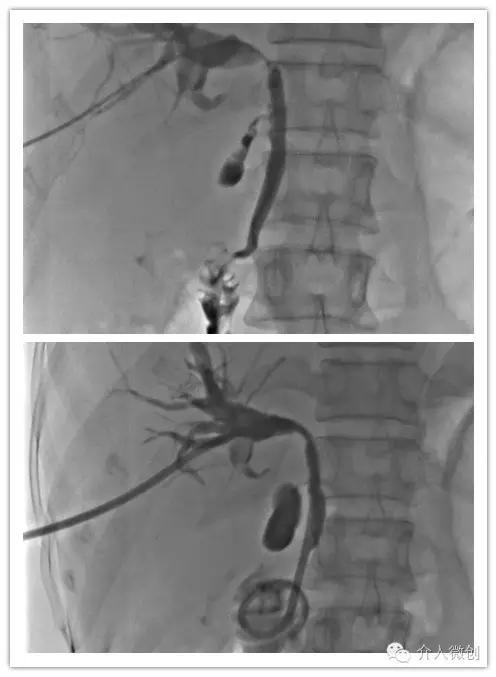

肝动脉化疗栓塞联合经皮瘤内注药有效控制肝脏转移瘤

05经皮胆道引流管置入术(PTCD)

中晚期肝癌常侵犯、压迫胆管导致出现梗阻性黄疸、继发胆道感染等,PTCD创伤小、见效快,可快速缓解梗阻症状、改善肝脏功能,且可为后续胆道支架植入等其它介入微创治疗打下良好基础,有效改善肿瘤晚期患者的生活质量。

肿瘤侵犯压迫肝门部胆管导致胆道梗阻,置入胆道引流管行胆汁引流减黄